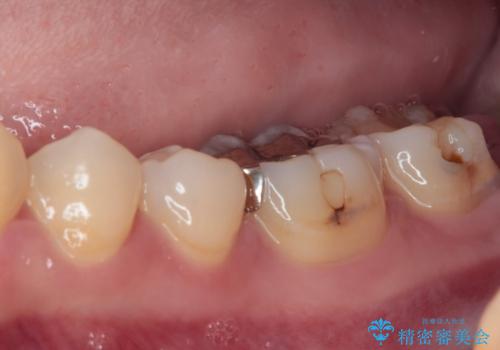

- 過去の歯医者通いの恐怖から虫歯を放置してきたものの、一大決心して来院された患者様です。

神経組織の失活している歯や歯根だけが残っている歯などがあり、全体的に歯石も多く付着している状態でした。

まずは歯石除去とブラッシング方法などの衛生指導を徹底的に行って口腔内環境を改善し、汚れの溜まりやすくなっている親知らずは全て抜去することとしました。

その後、歯根だけとなっている歯はインプラントに、神経組織の失活している歯は根管治療を行い、いずれもオールセラミッククラウンにて補綴治療を行うこととしました。